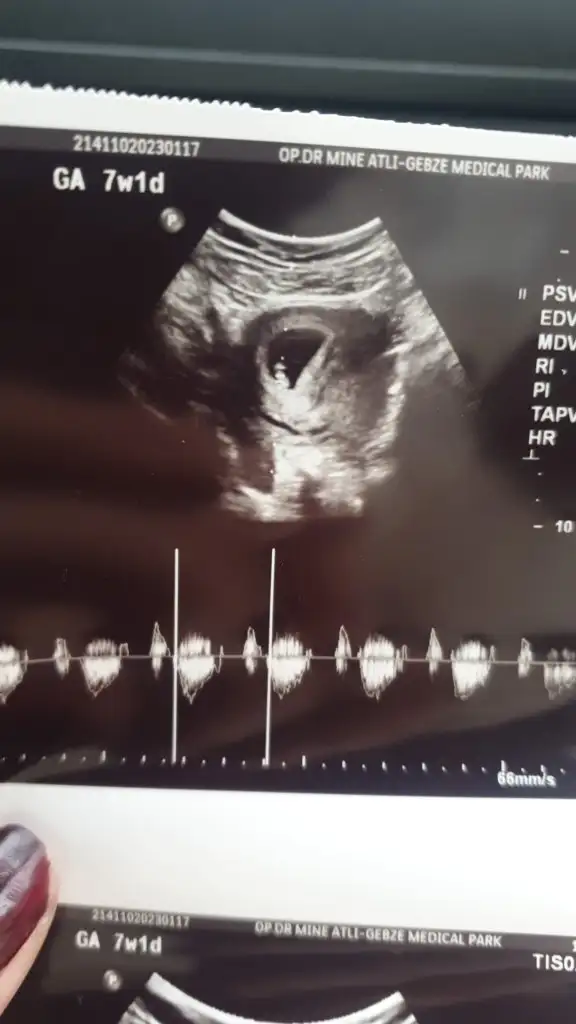

Kizlaaarr öncelikle Allah herkese bu duyguyu yaşatsın saglikla buyutsun bebelerini ben duydum bugün kalp atışını 6+6 haftalik dedi cok ritmik ve saglikli dedi cok şükür Allah'ıma cok mutluyum kizlarr🥰

• 20230117_110113.webp

20230117_110113.webp

18,4 KB · Görüntüleme: 88

Ayy maşallah maşallahhh 😍 şimdi buradaki atılan rahimin hangi konumunda tutunduguna göre cinsiyet tahmini diye bir fotoğraf vardi ya ? Ona göre sizinki erkek heheheh 🤭